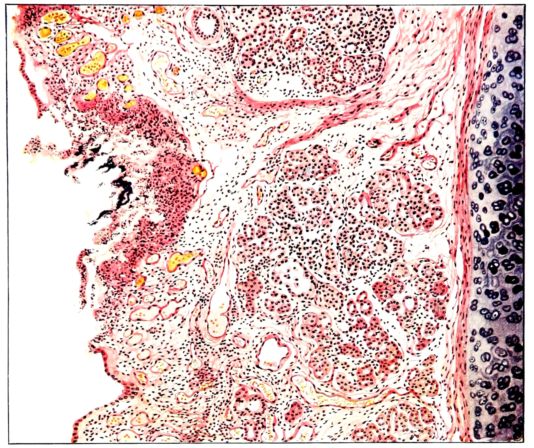

FIG. I. AUTOPSY NO. 99. ACUTE HEMORRHAGIC AND ULCERATIVE LARYNGOTRACHEITIS.

FIG. I. AUTOPSY NO. 99. ACUTE HEMORRHAGIC AND ULCERATIVE LARYNGOTRACHEITIS.

Early in the disease the congestion and the hemorrhages that have been described in the mucous membrane of the nasopharynx (14 and 94) are also conspicuous features in the lining of the trachea and bronchi (Fig. I). This membrane is swollen, turgid, red, and covered by a copious, mucous exudate which may be clear, but much more frequently is blood-stained or opaque and yellowish in color. The blood, variable in amount, may be fresh and red; and after the mucous exudate on the surface is removed, more intense red foci stand out on the congested base (47, 90, 157). Frequently, as the bronchi are approached, the red color of the mucosa becomes more intense and may have a garnet tinge. Membranes such as are encountered in the more usual necrotizing inflammatory processes, like diphtheria, have not occurred in the trachea and larger bronchi in this series (108, 128, 157).[3] The exudate peels off readily, and as indicated above, leaves a velvety red surface, 14dotted here and there with darker or more intensely red foci. Small ulcerations of the mucosa occur, but are inconspicuous (82, 156). As the finer ramifications of the bronchi are approached, the accumulation of the exudate in their lumina becomes more and more marked, and on cross section of the lung, they often stand out conspicuously on account of their increased size and projecting, seromucous, blood-stained content (101, 149, 162).